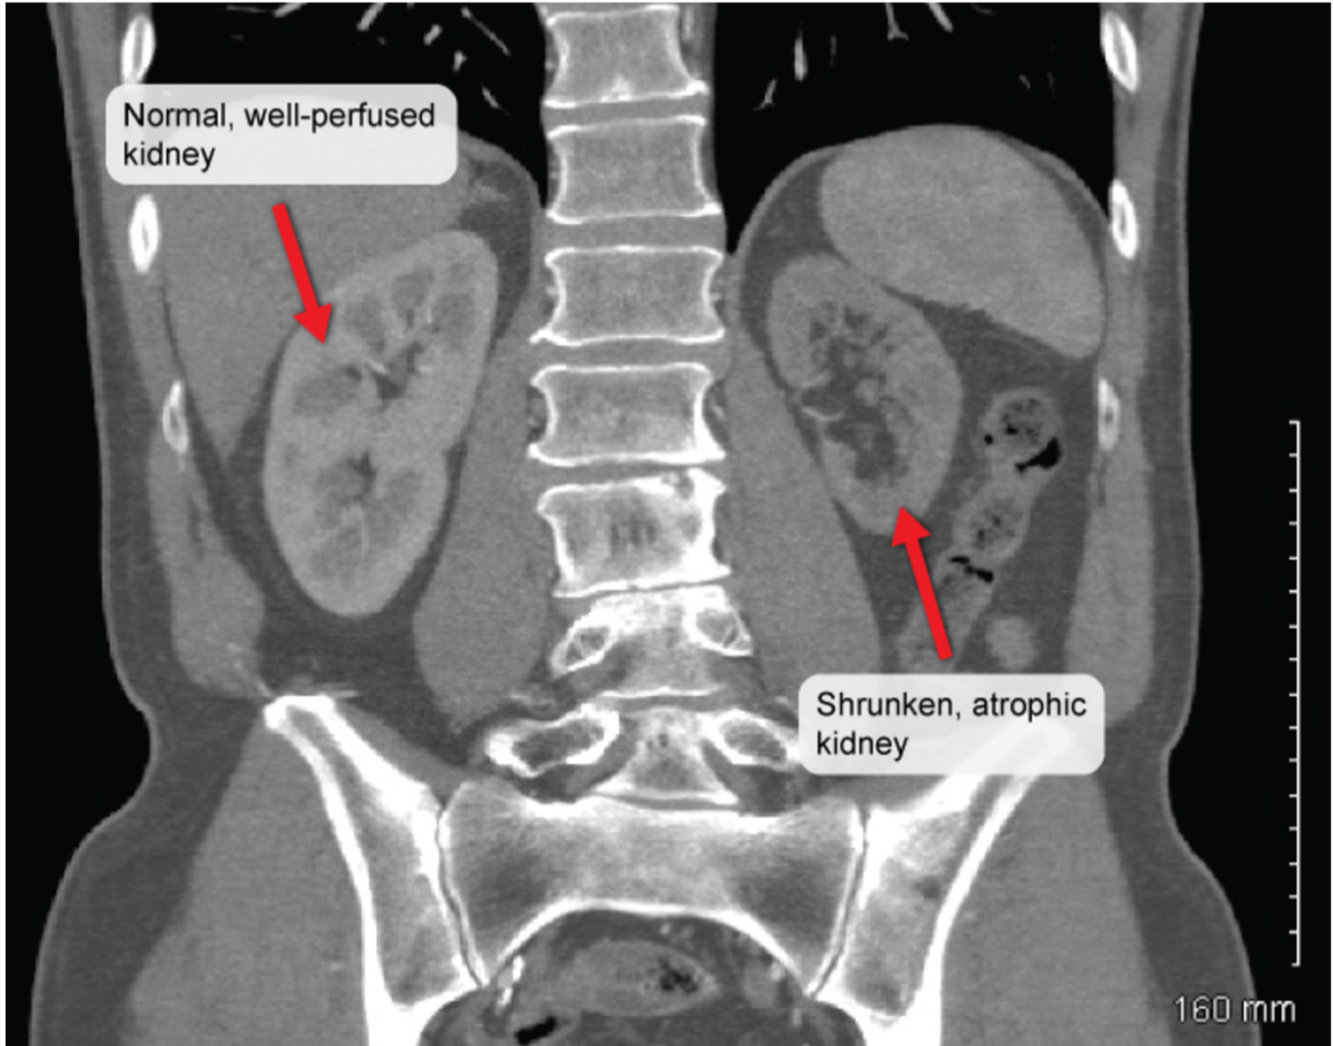

A 65 yo patient comes in complaining of abdominal pain after eating who has a BP of 175/110.

CT scan of the abdomen reveals the following:

What condition is this patient most likely suffering from?

Renal artery stenosis